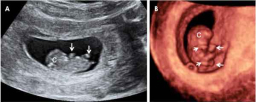

Qué se detecta en la eco de la semana 12

La ecografía de la semana 12 permite ver algunas malformaciones, como la translucencia nucal o engrosamiento de la nuca del feto, que puede indicar que el bebé no se desarrolla correctamente. Además de alteraciones cromosómicas, ¿la translucencia nucal puede hacer sospechar otras anomalías...

Ecografía de bebé de 11 semanas

Al empezar la semana 11 de embarazo el bebé mide unos 45 milímetros pero ya pueden visualizarse órganos muy pequeños como los dedos de las manos o de los pies. La ecografía puede detectar las malformaciones fetales denominadas mayores (en extremidades, abdomen...).